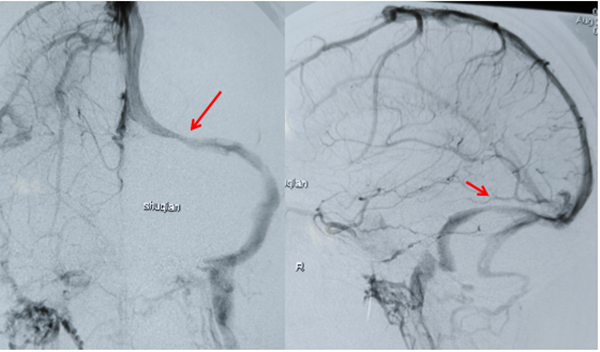

图1 术前造影发现左侧横窦狭窄(箭头处),狭窄两端压力差超过300mmH20